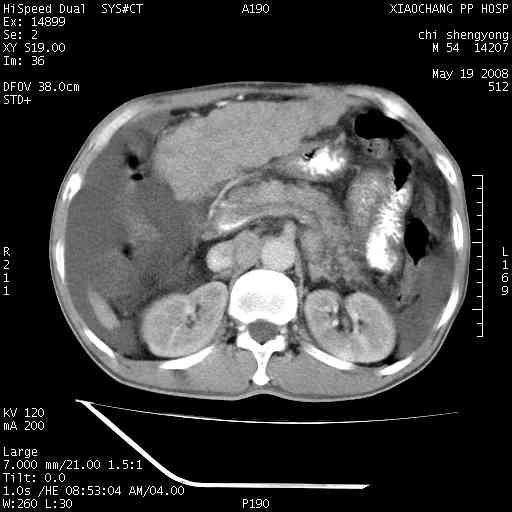

以下是引用zjzjr在2008-5-21 10:52:00的发言:[br]肝左叶巨块型肝癌伴门静脉左支瘤栓形成.肝硬化、腹水,胃底静脉曲张,脾术后改变。

以下是引用随光逐影在2008-5-21 16:20:00的发言:[br]1)肝左叶肝癌伴门静脉左支瘤栓形成,腹膜后淋巴结转移。2)肝硬化、腹水、胃底静脉曲张。3)胆囊炎。4)脾脏缺如,为切除术后所致。